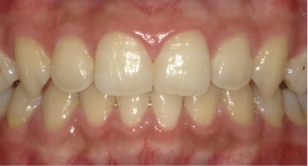

伊藤矯正歯科医院での安定した症例

これに対し伊藤矯正歯科医院では、抜歯を伴う矯正を行ったのちに何も装置を使用しなくて何年か経過しても、かなり安定している症例をみることが多くありました。(「安定調査症例1~4」と当HPの症例集ページ「叢生第3,4症例」をご覧下さい。)そこで治療が終わって数年経過した時点で、資料採得のできた14症例について歯並びの変化を観察しました。

これによると当院の治療後の歯並びの変化は、従来の矯正に比べ変化が非常に少ない事が分ります。つまり当院の矯正治療は、従来の矯正治療に比べ大変に安定していることが分かります。